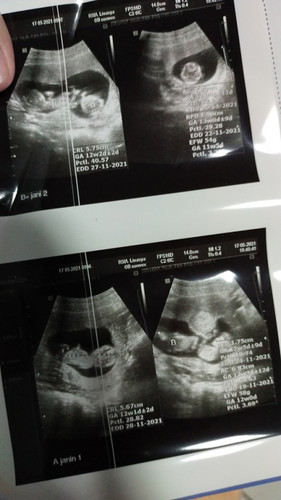

Sedih ya Bun,lagi hamil tapi harus LDR sama suami,karena kita beda negara indo-kuwait.dia harus ngelanjutin kuliahnya dulu,buat masa depan kita.pengen nya lagi hamil di manja suami,di pijit,di Elus,di suapin suami,dan sedih banget gara² covid,kuliah suamiku semakin lama,aku gabisa ikut dan lahiran di sana.karena kita baru nikah di negara ku.#firstbaby